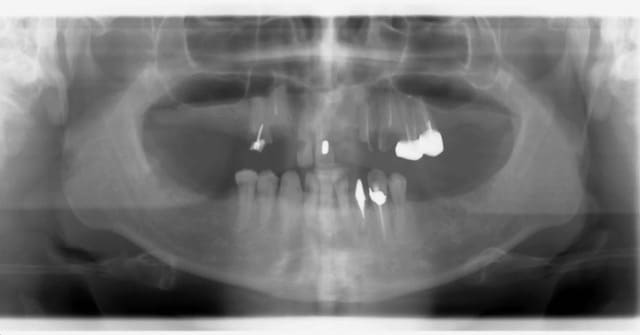

Patient de 35 ans

Il voulait tout refaire, mais pour une raison financiere il souhaitait faire le haut puis le bas. Je n'aime pas trop séparer les 2 arcades mais j'ai essayé de gerer au mieux.

Bref, le maxillaire a été traité par une pac immédiate qui aux dernieres nouvelles allait bien.

Mais il n'est pas encore revenu pour la réhabilitation de l'arcade mandibulaire.